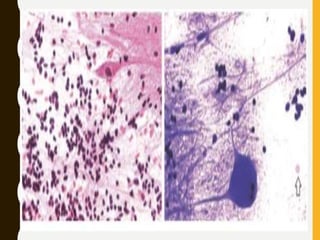

• Anaplastic astrocytoma. (a) Cryostat section showing freezing

artifact, nuclear distortion, and effacement of the fibrillary

background (Methylene blue)

• (b) Cytologic preparation from the same tumor showing beautifully

preserved nuclear and cytoplasmic details. Note the characteristic

multipolar astrocytic processes (Smear, H&E)